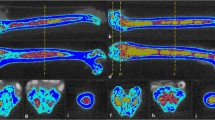

Figure 1 shows a typical MR spectrum collected in the vertebrae on clinical scanners. Based on peak assignment from high-resolution NMR spectroscopy in acylglycerol mixtures and MAT samples (35,36,37), lipid peaks I, IV, V, and VI are assigned to resonances of lipid protons at 0.90 ppm, 2.77 ppm, 4.20 ppm, and 5.31 ppm respectively. Peak II is assigned to the superposition of resonances at 1.30 ppm and 1.59 ppm, and peak III is assigned to the superposition of resonances at 2.03 ppm and 2.25 ppm. The water peak is at 4.7 ppm. From these peaks, two parameters can be derived to characterize the marrow fat:

a Single voxel MRS data in L2 using PRESS sequence at 1.5 Tesla (female, 92 years old). b Lipid peaks I, IV, V, and VI were assigned to resonance of lipid protons at 0.90 ppm [–(CH2)n–CH3)], 2.77 ppm [–CH=CH–CH2–CH=CH–], 4.20 ppm [–CH2–O–CO–], and 5.31 ppm [–CH=CH–], respectively. Peak II was assigned to the superposition of resonances at 1.30 ppm [–(CH2)n–] and 1.59 ppm [–CO–CH2–CH2–], and peak III was assigned to the superposition of resonances at 2.03 ppm [–CH2–CH=CH–CH2–] and 2.25 ppm [–CO–CH2–CH2–]. The water peak was at 4.7 ppm. The spectrum was fitted using Voigt model (left column), pure Lorentzian model (middle column), and pure Gaussian model (right column). Blue, red, and green curves represent the experimental spectrum, the fitting spectrum, and the spectra of separated components, respectively. Fitting residuals are plotted in black and enlarged in bottom row (adapted from reference (48))

The in vivo MRS data analysis for accurate fat quantification in bone marrow, especially fat composition, is challenging due to line broadening caused by susceptibility differences between bone and marrow, and superposition of spectral peaks. Peak area integration has been used, which however has limited capability of quantifying overlapping peaks (38,39,40). Peak fitting methods using LC models with pre-defined base-sets (41, 42) or using line-shape models with prior information in either frequency-domain (26•, 43, 44) or time-domain (45, 46) can help to improve the quantification accuracy. Previous studies with line-shape model fitting mostly used Lorentzian or Gaussian models for the fitting. A recent study showed that using Voigt model reduced the fitting error by 33.8% and 32.3% compared with using Lorentzian and Gaussian models respectively (47) (Fig. 1b). Using Voigt models and time-domain fitting, a fully automatic algorithm was developed with high reliability and repeatability of quantifying MAT contents and composition even for data collected at 1.5 Tesla (47). Other factors affecting fat contents or composition evaluation include the different T2 weights of water and lipids in spectrum acquired with single TE. Acquiring data with multiple TEs will allow T2 correction (48•).